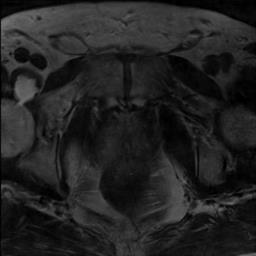

Modern deep neural networks struggle to transfer knowledge and generalize across diverse domains when deployed to real-world applications. Currently, domain generalization (DG) is introduced to learn a universal representation from multiple domains to improve the network generalization ability on unseen domains. However, previous DG methods only focus on the data-level consistency scheme without considering the synergistic regularization among different consistency schemes. In this paper, we present a novel Hierarchical Consistency framework for Domain Generalization (HCDG) by integrating Extrinsic Consistency and Intrinsic Consistency synergistically. Particularly, for the Extrinsic Consistency, we leverage the knowledge across multiple source domains to enforce data-level consistency. To better enhance such consistency, we design a novel Amplitude Gaussian-mixing strategy into Fourier-based data augmentation called DomainUp. For the Intrinsic Consistency, we perform task-level consistency for the same instance under the dual-task scenario. We evaluate the proposed HCDG framework on two medical image segmentation tasks, i.e., optic cup/disc segmentation on fundus images and prostate MRI segmentation. Extensive experimental results manifest the effectiveness and versatility of our HCDG framework.